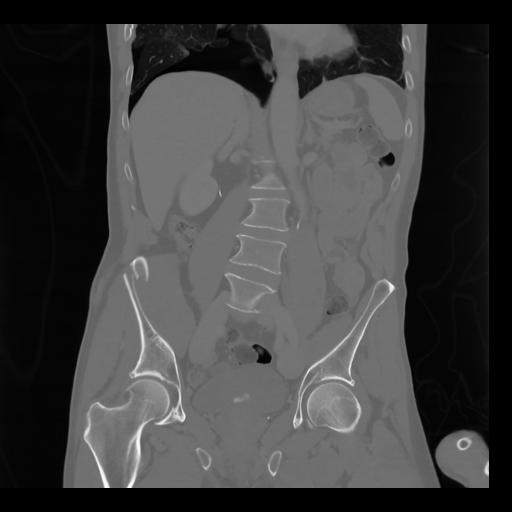

35 CUERPO,CE,Coronal,3.000,CUERPO,Coronal,